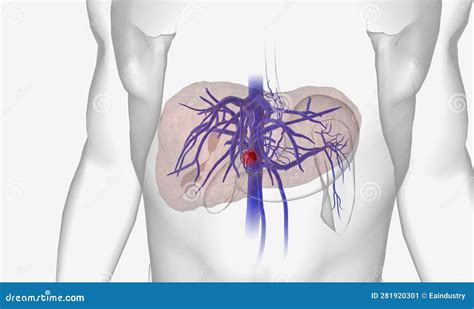

Portal Vein Thrombosis (PVT) is a serious medical condition characterized by the formation of a blood clot within the portal vein, the major vessel responsible for carrying blood from the gastrointestinal tract and spleen to the liver. When this vessel becomes blocked or narrowed by a thrombus, it can disrupt normal blood flow, potentially leading to increased pressure in the portal venous system—a condition known as portal hypertension—and severe complications if left untreated. Understanding the causes, symptoms, and treatment options for this condition is crucial for both patients and healthcare providers, as early detection significantly improves clinical outcomes.

The primary goal in treating Portal Vein Thrombosis is to restore blood flow to the liver, prevent the clot from propagating further, and manage the complications arising from portal hypertension.

• Interventional Radiology: In severe, treatment-resistant cases, procedures such as Transjugular Intrahepatic Portosystemic Shunt (TIPS) may be necessary to bypass the obstructed vein and relieve portal hypertension.